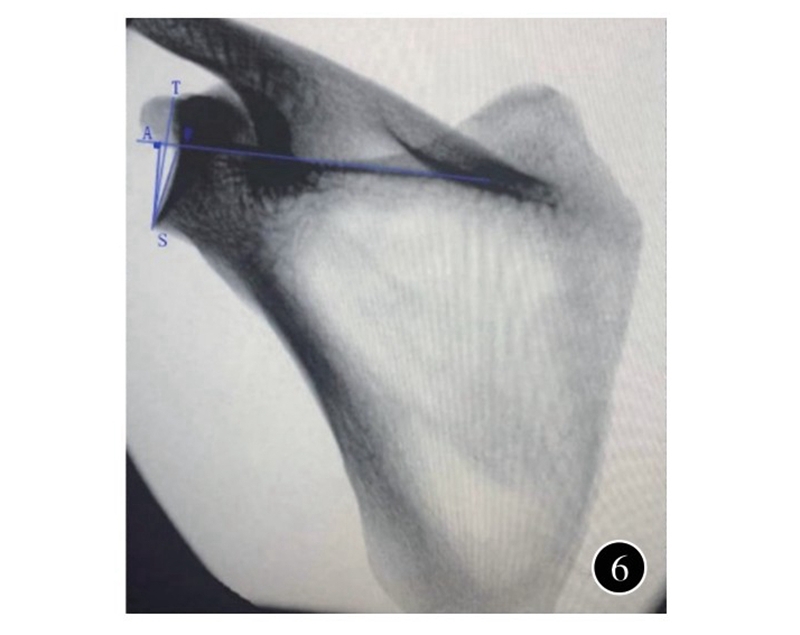

一般认为,肩胛盂关节面有5~7°的向上倾斜;但由于肩胛骨的位置和解剖的不规则,很难准确描述测量标准。在肩胛骨骨折中,有人用盂极角(glenopolar angle,GPA)来描述肩胛盂倾斜的变化;但其为间接测量,应用也局限。有人用肩胛盂最高点至最低点的连线,与冈上窝底的夹角来评估肩胛盂向上的倾斜,也被称为β角,代表了肩胛盂整体在冠状面的倾斜程度,在肩胛骨正位X线和三维CT测量中具有极佳的准确性和可重复性。更进一步,肩胛盂最高点至最低点的连线与冈上窝底垂线的夹角被称为全肩关节成形角(total shoulder arthroplasty angle,TSA角),与β角互为余角,同样用于评估肩胛盂向上的倾斜(图6)。根据其倾斜的方向,又分为向上倾斜和向下倾斜,代表肩胛盂的倾斜程度,在肩关节成形术前规划中较为重要。肩胛骨前后位X线、二维CT和三维CT均被用于测量肩胛盂在冠状面上的倾斜,但以三维CT测量所得数据最为精确。肩关节退变患者TSA角的测量均值为7.68~12°;正常人群TSA角为2~5.3°。在反肩关节成型术中,基座一般放置在肩胛盂下部,因而Boileau等提出了反肩关节成型角(reverse shoulder arthroplasty angle,RSA角)(图6) ,即肩胛盂下部连线与冈上窝底垂线之间的夹角,能更加精确评估肩胛盂下部形态。他们测量肩关节退变患者RSA角的测量为20°,较TSA角大8°。骨性关节炎、肩胛盂磨损行肩关节成型术前需行三维CT重建用于测量肩胛盂磨损导致的肩胛盂倾斜的改变,精准评估肩胛盂情况。

图6 肩胛骨正位X线用于测量肩胛盂向上倾斜的示意图。

全肩关节成形角为肩胛盂最高点至最低点的连线与冈上窝底垂线的夹角;反肩关节成型角为肩胛盂下部连线与冈上窝底垂线之间的夹角